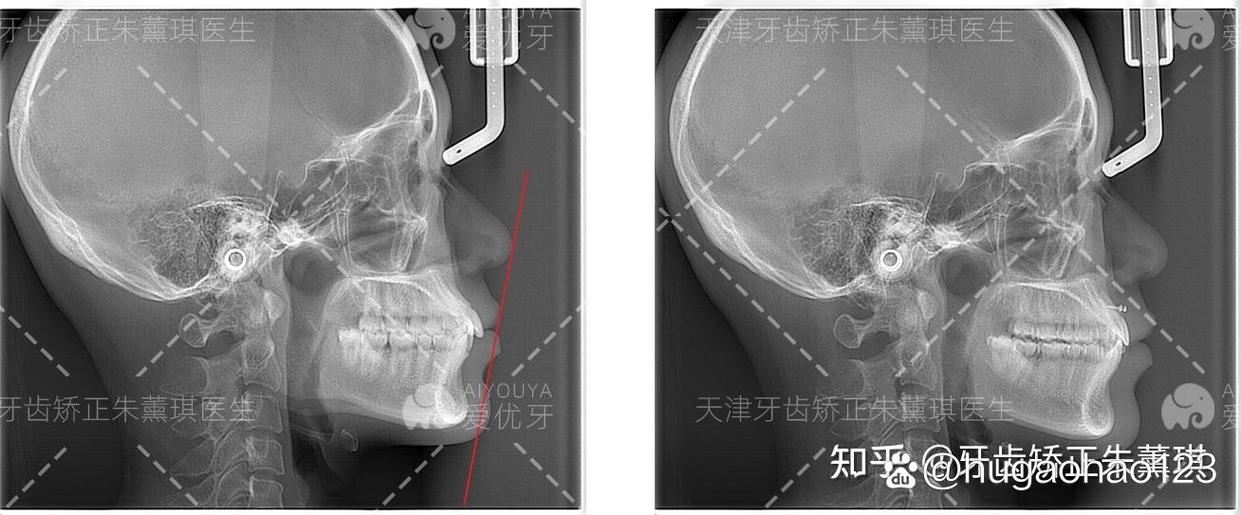

正畸治疗是一个系统的过程,天津口腔医院建立了标准化的治疗流程,确保每一步都精准规范,初诊阶段,医生会通过口腔检查、X光片(曲面断层片、头颅侧位片)、口内扫描及面部照相等方式,全面评估患者的牙齿排列、颌骨关系、面部美学及牙周状况;方案设计阶段,结合数字化模拟结果与患者需求,制定个性化的治疗计划,明确治疗目标、周期及费用;矫治器制作与粘接阶段,根据方案选择合适的矫治器,传统托槽需精准粘接于牙面,隐形矫正则通过3D打印定制一系列透明牙套;主动治疗阶段,患者需按医嘱定期复诊(传统托槽每4-6周,隐形矫正每6-8周),医生通过调整矫治力引导牙齿移动;治疗结束后进入保持阶段,需佩戴保持器2年以上,防止复发。